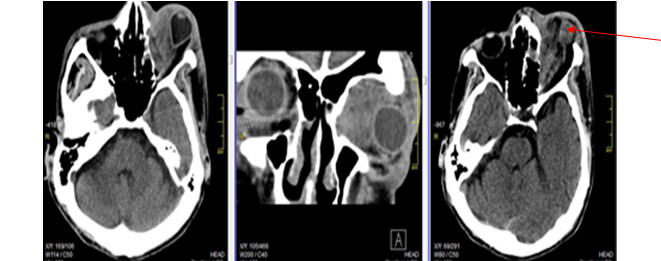

Volver a los detalles del artículo Linfoma primario de la órbita. Informe de un caso